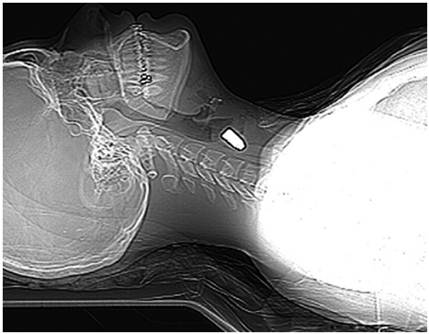

Paciente femenina de 20 años de edad, sin antecedentes relevantes, quien presentó una herida cervical de 4 x 3 cm en la región submaxilar izquierda, secundaria a proyectil de arma de fuego, con orificio de entrada en el triángulo muscular y sin orificio de salida (figura 1). Al examen físico se encontraba taquicárdica, con cifras tensionales normales (129/80 mm/Hg), sin “signos duros” de trauma ni “signos blandos” (disfagia, disfonía, hemoptisis o ensanchamiento mediastinal). Por tratarse de un trauma penetrante de cuello secundario a un proyectil de arma de fuego y por su localización, se consideró que tenía compromiso de planos profundos y una alta probabilidad de lesión orgánica (figura 2).